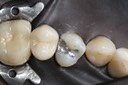

Ted Kanamori #24 finish